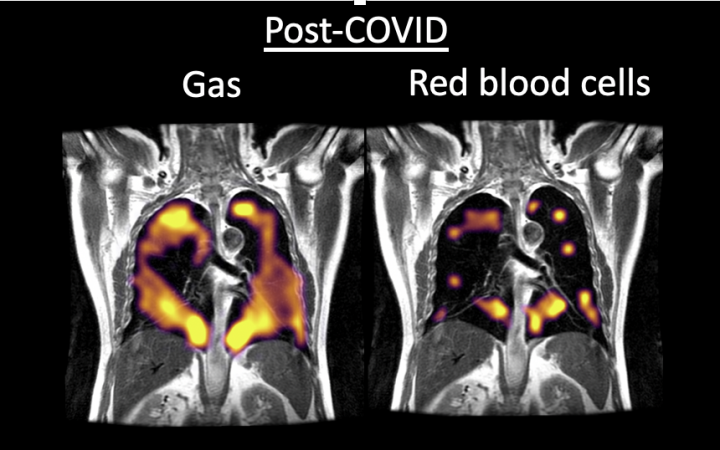

Las resonancias magnéticas realizas muestran daño pulmonar en áreas en las que el aire no fluye fácilmente hacia la sangre. Motivo por el que los ocho pacientes manifestaban tener sensación de falta de aire

Pero sin duda alguna los pulmones continúan siendo los órganos más afectados. Un grupo de investigadores pertenecientes a las Universidades de Oxford y Sheffield (Reino Unido), han empleado una innovadora técnica de resonancia magnética que trabaja con xenón hiperpolarizado. Una técnica con la que se ha podido apreciar que las secuelas ocasionadas por la Covid-19 en los pulmones de las personas que consiguen superar la enfermedad son mucho más graves de lo que se pensaba hasta el momento.

Este hallazgo explicaría el origen de la disnea o fatiga persistente que muchas personas afirman continuar padeciendo a pesar de haberse curado. Y esto hace pensar a los investigadores que el nuevo coronavirus podría estar afectando a las funciones pulmonares de una forma mucho más grave de la que se pensaba.

El estudio ha tomado como base a 10 pacientes con edades comprendidas entre los 19 y los 69 años. Mediante la técnica descrita, que permite que los pacientes inhalen el xenón durante la exploración mediante resonancia magnética, el equipo liderado por Fergus Gleeson encontró que ocho de los 10 pacientes presentaban disnea y cansancio persistente tres meses después de haberse infectado. Cabe señalar que ninguno de estos ocho pacientes había requerido el ingreso en UCI y tampoco la asistencia de ventilación mecánica. Además, en las exploraciones convencionales realizadas en estos por profesionales médicos no se había detectado ningún tipo de anomalía en sus pulmones.

Las resonancias magnéticas realizas muestran daño pulmonar en áreas en las que el aire no fluye fácilmente hacia la sangre. Motivo por el que los ocho pacientes manifestaban tener sensación de falta de aire. Los resultados de este estudio han sentado las bases para una ampliación del mismo con una muestra inicial de 100 sujetos para confirmar los hallazgos. Unos datos especialmente relevantes que podrían explicar los motivos por los que muchas personas continúan presentando dificultades respiratorias o cansancio extremo meses después de haber superado la enfermedad.